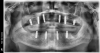

Impressions using an intraoral optical scanner (TRIOS®, 3Shape, [alternatively: iTero®, Align Technology; i700, Medit]) were made of the patient's maxillary and mandibular dentition. Photographs were taken, and a cone-beam computed tomography (CBCT) scan was made. The CBCT images were manipulated using a dental implant planning software (Invivo, Anatomage, [alternatively: Implant Studio®, 3Shape; exoplan, exocad]), and virtual implants were planned for placement into widely distributed and spaced regions of the maxillary and mandibular arches (Figure 3). Virtual implants were virtually placed into the positions of teeth Nos. 2, 4, 6, 11, 13, and 15 in corresponding maxillary root sockets and the positions of teeth Nos. 19, 22, 27, and 30 in corresponding mandibular root sockets.

Fig 3. After a CBCT scan was made, virtual implants were placed in widely distributed positions on the maxillary (six implants) and mandibular (four implants) arches.

Figure 3